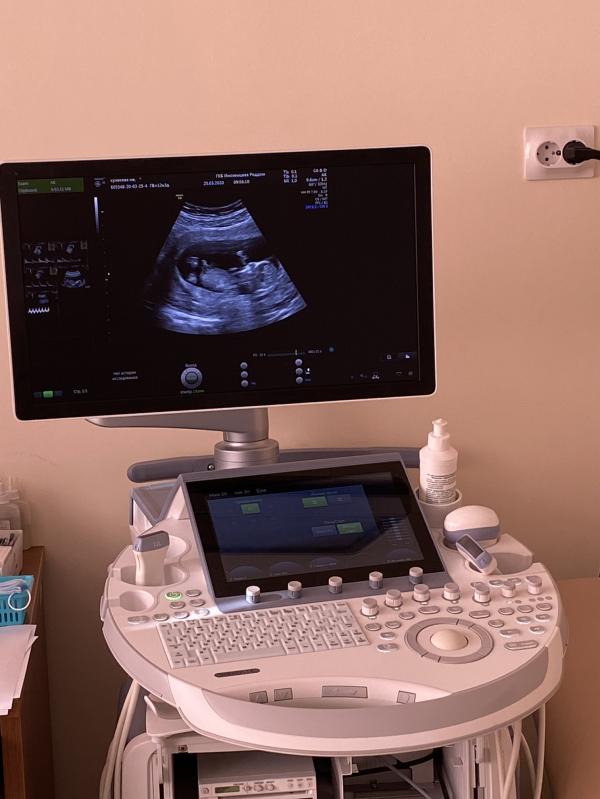

Ух, девочки, пережили мы сегодня первый скрининг, хоть и второй раз, но это так волнительно, прям жуть. Немного расстроена тем, что пол не сказали малыша, с дочей уже в 11 недель сказали, а сегодня сказали в 15-16 недель. Может есть у вас какие-то признаки по которым можно понять кто живет в животике? 🥰

Есть ещё фото, но там плохо видно копчик и бугорок) хорошо, обязательно 😆

если я правильно вижу бугорок, то мальчик)